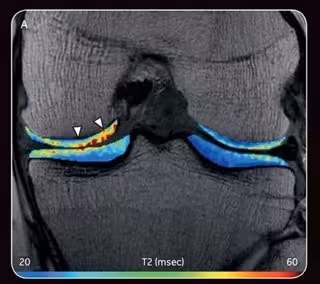

La Liga norteamericana de baloncesto (NBA) y GE Healthcare han decidido colaborar promoviendo la investigación médica ortopédica y del deporte, con el objetivo de beneficiar la salud de los jugadores de la NBA y de atletas de todos los niveles, enfocándose en la salud de las articulaciones, lesiones agudas y desgaste musculoesquelético.

Además, la NBA y GE también destinarán fondos para investigadores clínicos que estudian técnicas diagnósticas y preventivas para identificar riesgos de desarrollo de problemas ortopédicos y conocer mejor las lesiones por desgaste.